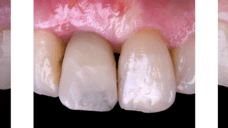

The main issue involved the upper right central incisor (tooth 1.1), which was devitalized and presented recurrent abscesses. Clinical and radiographic evaluation confirmed the presence of buccal bone wall resorption, leading to a significant defect in the alveolar ridge. This condition compromised both the hard tissue and the surrounding soft tissue, posing a challenge for achieving long-term stability and esthetic success in the anterior maxilla.

Due to the tooth’s location in the esthetic zone, the resorption and recurrent infections had a direct impact on the patient’s smile and overall confidence. She expressed dissatisfaction with the appearance of the affected tooth and emphasized the importance of restoring function and esthetics quickly. The clinical presentation highlighted the need for a treatment plan that combined immediate implant placement with simultaneous hard and soft tissue management to address the complex requirements of this case.